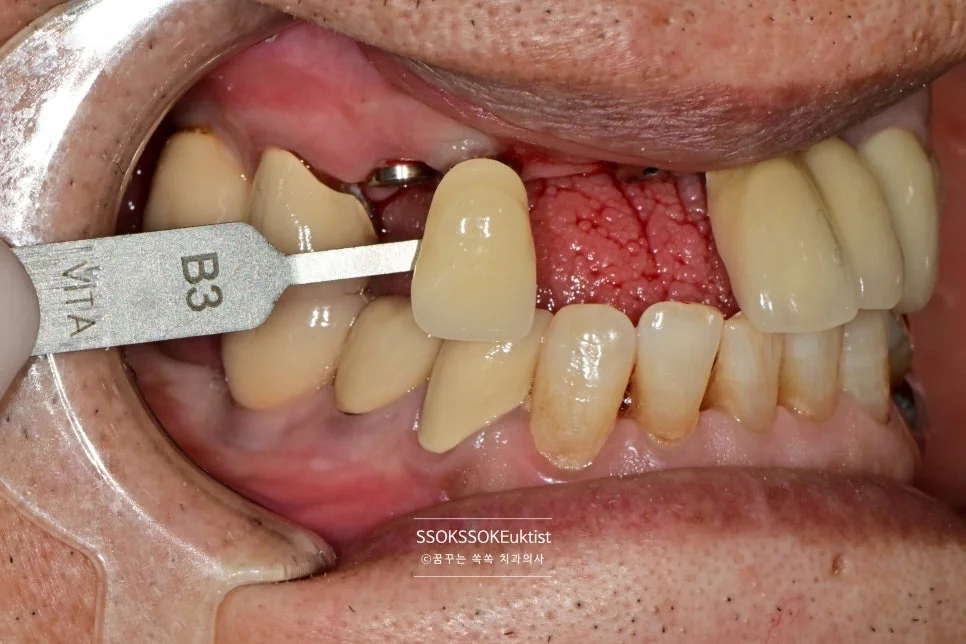

Step 7. 쉐이드 매칭 (색상 결정)

쉐이드 가이드로 최적의 색상 매칭

앞니는 색상 또한 너무 중요하기에 가장 적합한 색상을 shade-guide 기준으로 기록하고 최종 보철물을 의뢰합니다.